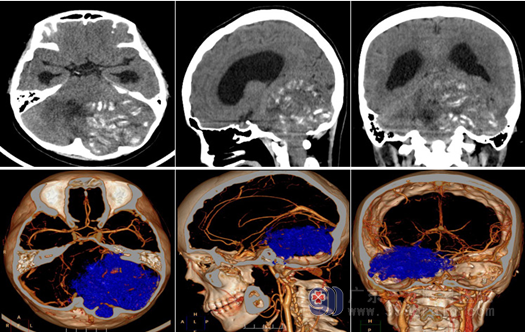

头颈部CTA检查:左侧小脑半球、左侧桥臂巨大占位性病变突入椎管内,病变内可见多发条状不匀钙化影,其内及周围示多发细小血管影,双侧椎动脉及颈总动脉开口位置正常;邻近枕骨受压变薄。